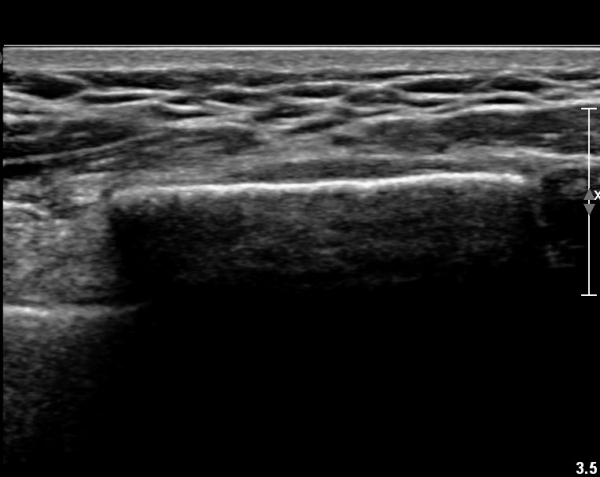

ŽÃËÀÚ¸¦ ¾à°£ ¸»´ÜÀ¸·Î À̵¿ÇÏ´Ï ¿¬ºÎÁ¶Á÷ ºÎÁ¾ÀÌ ´õ¿í ½ÉÇÏ°Ô °üÂûµÇ°í(»çÁø 2),